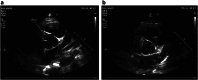

Methods and results: Even in recent Italian history, unexpected deaths continue to affect athletes but surprisingly any real knowledge regarding the numbers and the impact of those tragedies must take medical literature and non-medical press into consideration. Herein we report the clinical case of a 13-year-old patient with a bicuspid aortic valve, whose mother was alarmed by the news of a young boy who died because of an anomalous origin of coronary artery (AOCA) which had not been diagnosed at transthoracic echocardiography (TTE). Her obstinacy induced the physicians to repeat TTE and led to the same diagnosis in her son: actually, his right coronary artery originated from the opposite sinus of Valsalva. The suspicion was confirmed by coronary CT scan and, thanks to appropriate therapy, the boy now fares well.

Conclusions: AOCA is the second most common cause of sudden death in young athletes. Although AOCA is often undetectable at ECG, TTE increases sensitivity of preparticipation screening. It could therefore allow us to avoid such coincidences and prevent sudden juvenile death.